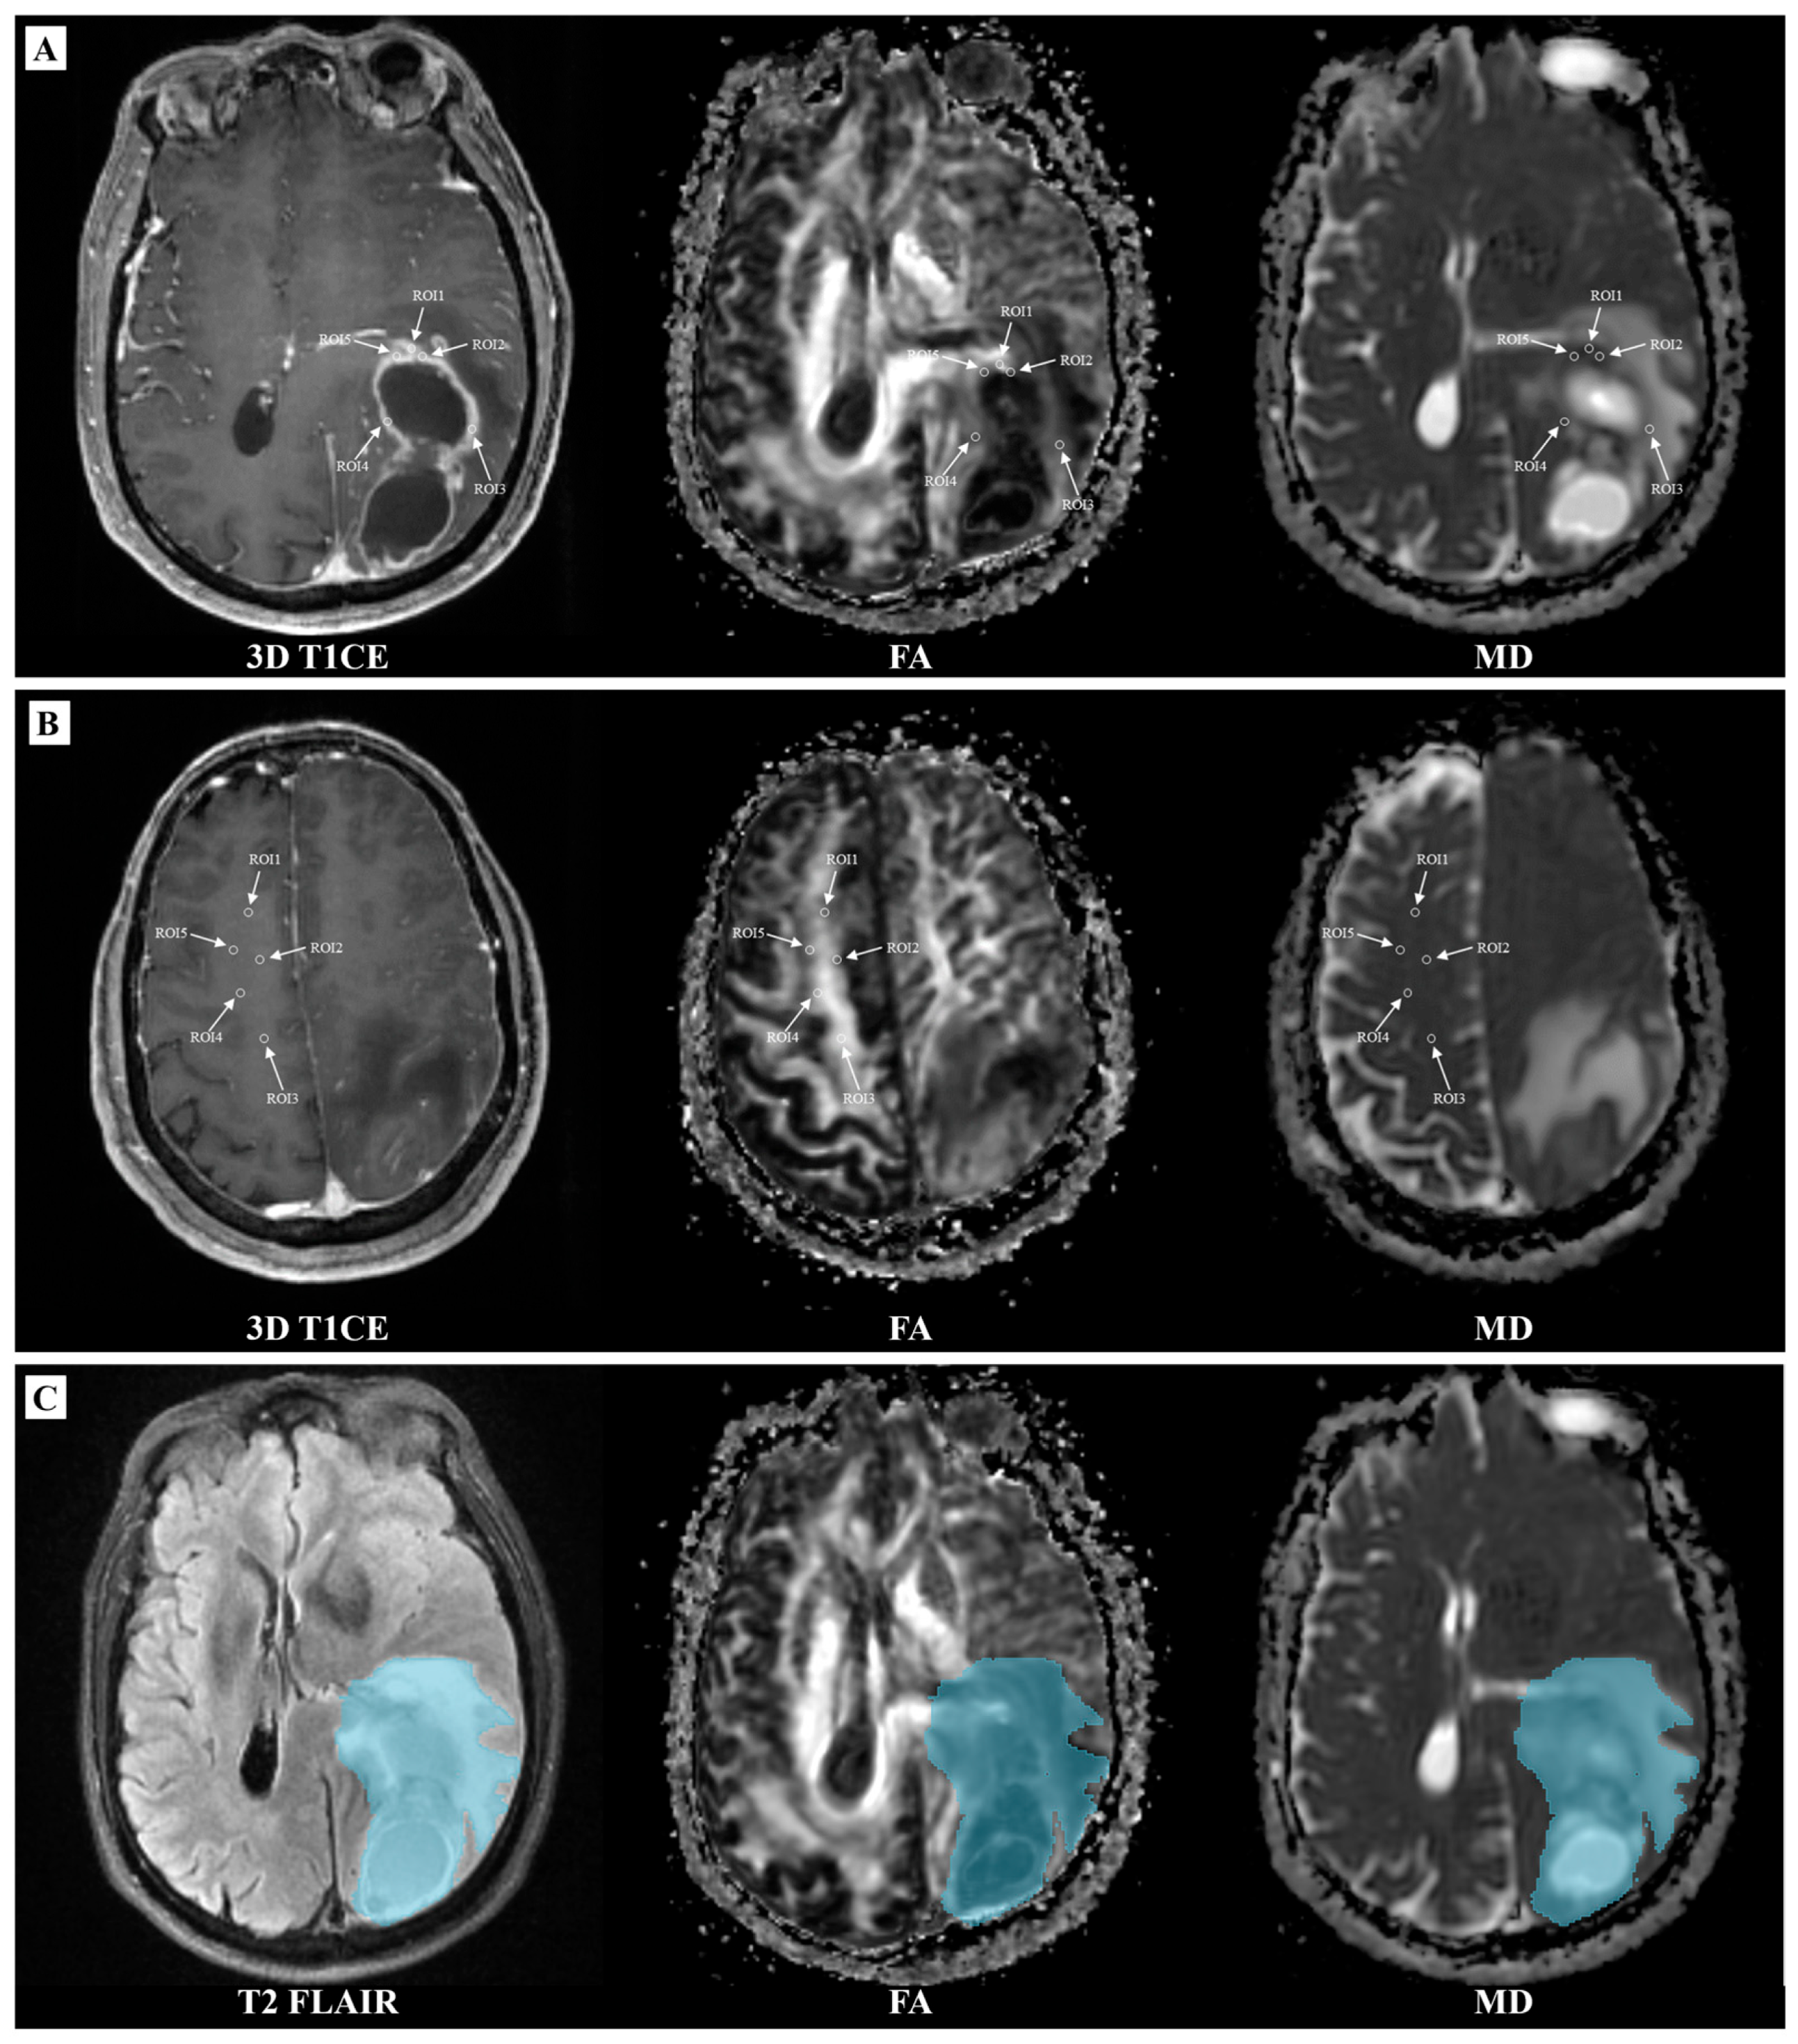

2.3. Imaging Analysis